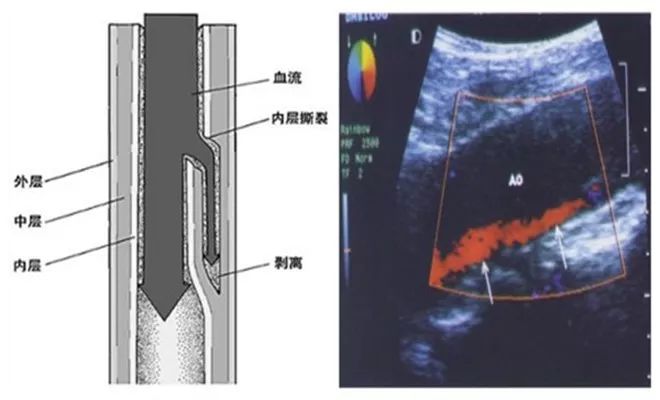

3. 股动脉夹层

股动脉夹层一般发生在患者具有动脉粥样硬化以及血管弯曲等情况时,手术过程中送入钢丝、鞘管或导管遇到阻力后强行送入导致,严重者可以合并血管周围大出血。

股动脉夹层为逆行而上,不久将自动闭合。

图4. 股动脉夹层。